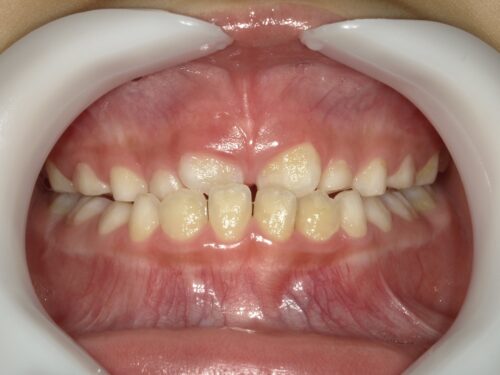

さらに1年後の写真です。

上下とも前歯は全て大人の歯に生え変わりました。

噛み合わせも歯並びも大きな異常はありません。

治療前後で比較します。

今後は全ての歯が永久歯に変わるまで歯科検診と合わせて定期的にチェックしていく予定です。

今回のように早い段階で治療に介入できると、治療期間も長期にかからずに済む場合があります。

もし、全て永久歯に変わってからの相談であれば、骨格的な問題が出ている可能性があり、通常の矯正では治せないこともあります。